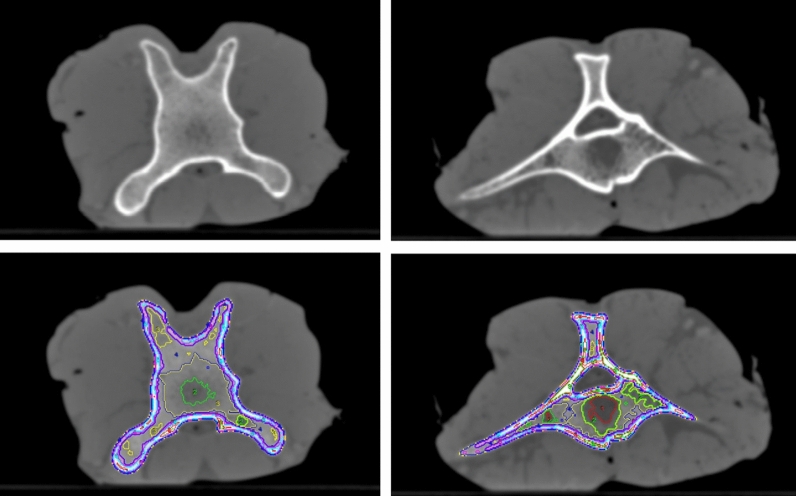

Bone segments of various bone densities (evaluation shown in Fig. 2a) were delimited by thresholding to determine the energy dependence of bone tissues in wide range of bone densities. This allows appropriate selection of data and thus phantom materials for differently hard (mostly spongious) bone found in different areas of the body. The bone tissue was segmented in density intervals with a width of 200 HU starting at -50 HU corresponding to a central value of 50 HU in the 120 kV volume. Thus, the softest bone measured corresponds to voxels within bone tissue with 50 ± 100 HU, the densest one to CT numbers exceeding 1850 ± 100 HU at the reference tube potential of 120 kV. However, in the porcine tibial head even denser bone was found that could be evaluated allowing to define an extremely dense bone section with above 1950 HU (mean value at 120 kV: 2017 HU). In the bovine ribs bone tissue from 250 HU (central value) to > 1550 HU was present, in the bovine vertebrae from 50 to > 1350, and in the porcine tibial head from 50 to > 1950 HU. Figure 7 illustrates the segmentation showing two slices of two different bovine vertebral bodies from the oxtail sample as an example. Segmentation and the definition of ROIs for HU evaluation was always performed in the scan volume acquired with 120 kV, and transferred to all other scans of the same sample, i.e., those acquired with the other tube potentials, after registration to ensure exactly equivalent ROI placement.

Figure 7.

Segmentation of areas with different bone densities using thresholding on the 120 kV image volumes. Example shows two slices from bovine vertebral bodies in the oxtail sample. Upper row: CT image, lower row: CT slice with regions of interest defining the bone density segments.